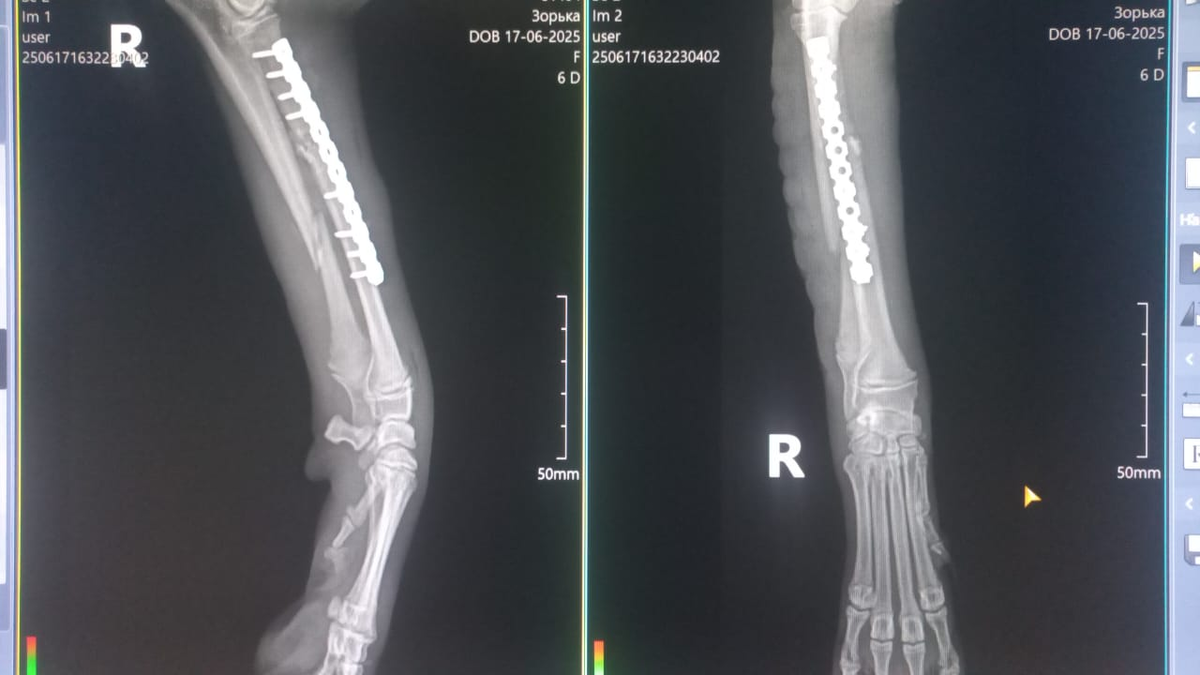

Рентген щеночка Зорьки.

После операции на лапке Зорька оставлена в ветклинике под присмотром. Она вышла из наркоза, состояние удовлетворительное. Завтра после осмотра нам подскажут когда её можно будет забрать и другие подробности.